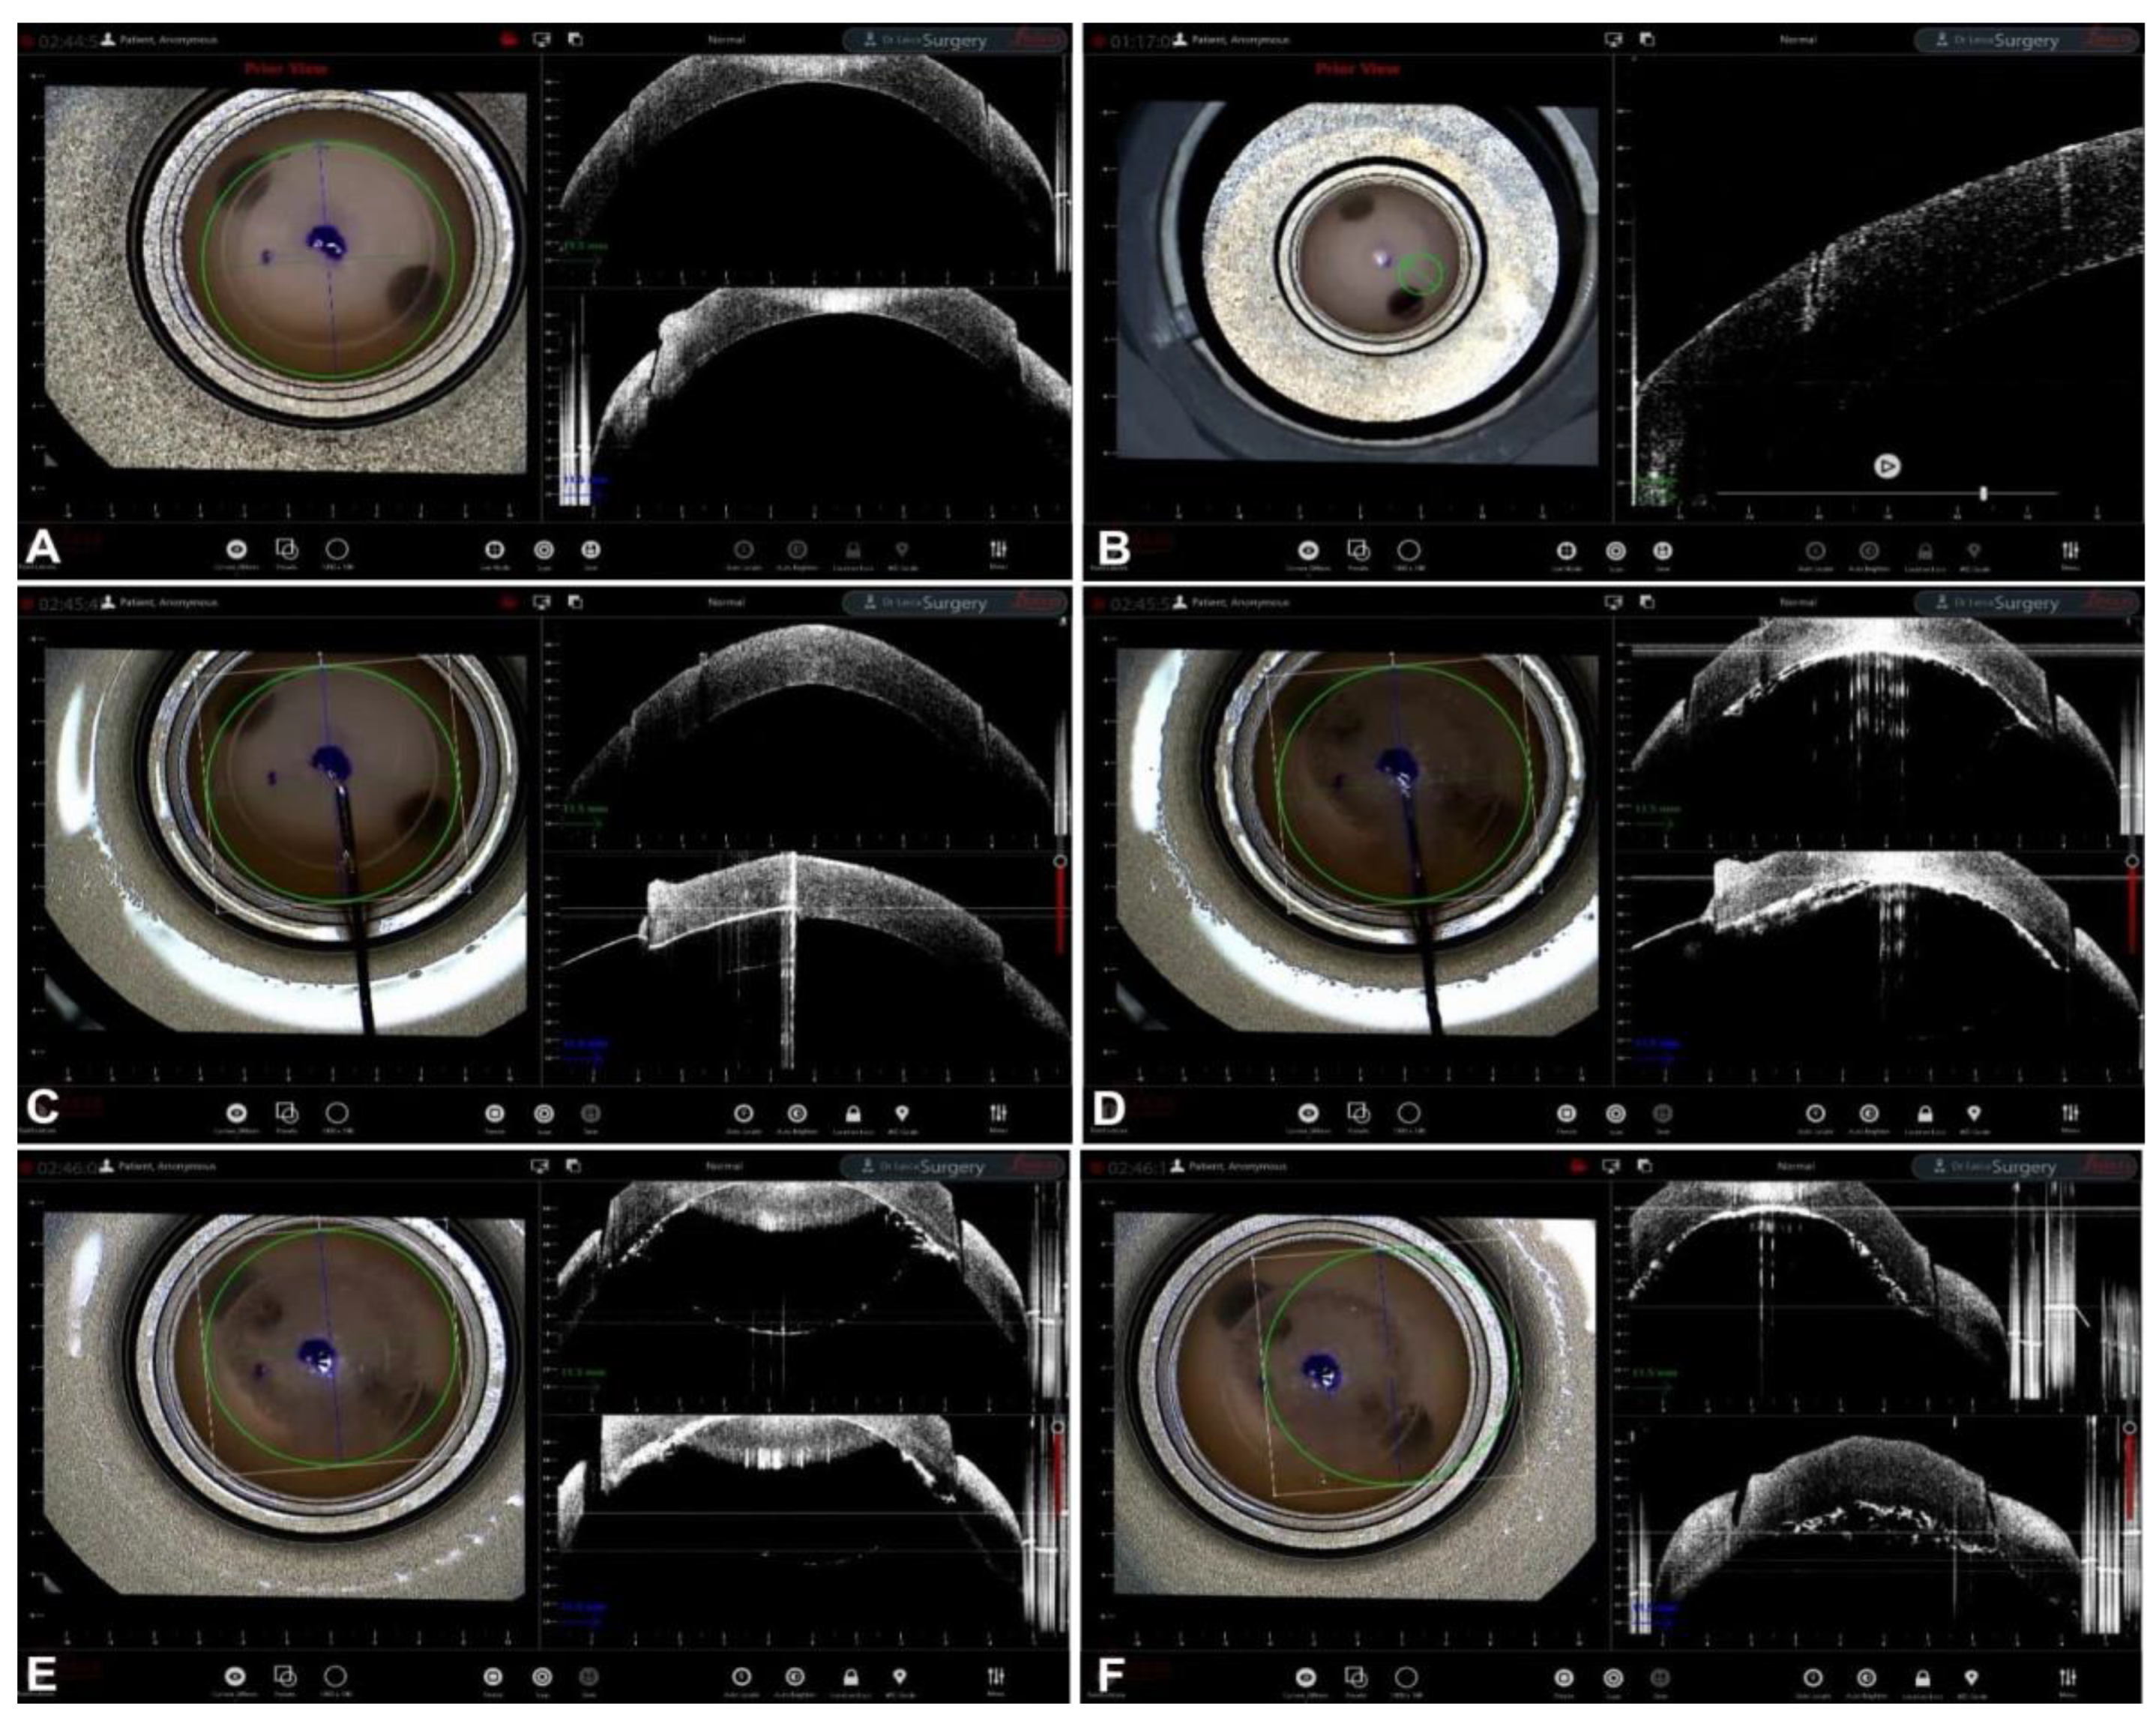

Guiding Big-Bubble Deep Anterior Lamellar Keratoplasty (BB-DALK)

- Santorum, P.; Yu, A.C.; Bertelli, E.; Busin, M. Microscope-Integrated Intraoperative Optical Coherence Tomography–Guided Big-Bubble Deep Anterior Lamellar Keratoplasty. Cornea 2021, 41, 125–129. [Google Scholar] [CrossRef]

- Scorcia, V.; Busin, M.; Lucisano, A.; Beltz, J.; Carta, A.; Scorcia, G. Anterior Segment Optical Coherence Tomography–Guided Big-Bubble Technique. Ophthalmology 2013, 120, 471–476. [Google Scholar] [CrossRef] [PubMed]

- Myerscough, J.; Friehmann, A.; Busin, M.; Goor, D. Successful Visualization of a Big Bubble during Deep Anterior Lamellar Keratoplasty using Intraoperative OCT. Ophthalmology 2019, 126, 1062. [Google Scholar] [CrossRef] [PubMed]

- Altaan, S.L.; Termote, K.; Elalfy, M.S.; Hogan, E.; Werkmeister, R.; Schmetterer, L.; Holland, S.; Dua, H.S. Optical coherence tomography characteristics of different types of big bubbles seen in deep anterior lamellar keratoplasty by the big bubble technique. Eye 2016, 30, 1509–1516. [Google Scholar] [CrossRef] [PubMed]

- Steven, P.; Le Blanc, C.; Lankenau, E.; Krug, M.; Oelckers, S.; Heindl, L.M.; Gehlsen, U.; Huettmann, G.; Cursiefen, C. Optimising deep anterior lamellar keratoplasty (DALK) using intraoperative online optical coherence tomography (iOCT). Br. J. Ophthalmol. 2014, 98, 900–904. [Google Scholar] [CrossRef] [PubMed]

- Au, J.; Goshe, J.; Dupps, W.J.; Srivastava, S.K.; Ehlers, J.P. Intraoperative Optical Coherence Tomography for Enhanced Depth Visualization in Deep Anterior Lamellar Keratoplasty from the PIONEER Study. Cornea 2015, 34, 1039–1043. [Google Scholar] [CrossRef][Green Version]